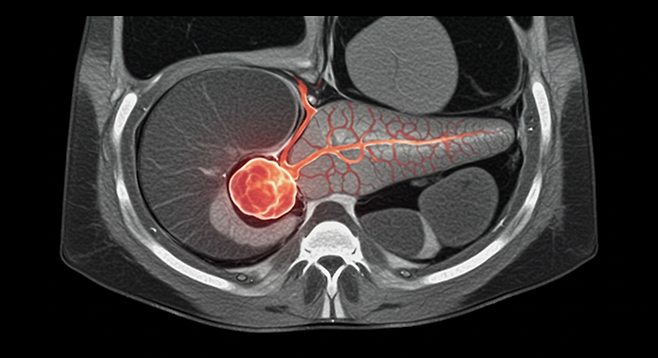

침묵의 장기, 췌장이 보내는 위험 신호: 초기 췌장염, 놓치지 마세요

췌장은 우리 몸에서 소화 효소와 호르몬(인슐린)을 생산하는 중요한 장기입니다. 췌장염은 이러한 췌장에 염증이 생기는 질환으로, 초기에는 증상이 미미하여 간과하기 쉽습니다. 하지만 방치하면 심각한 합병증을 초래할 수 있으므로, 초기 증상을 인지하고 적절한 대처를 하는 것이 중요합니다.

- 즉시 병원 방문: 소화기내과 전문의에게 진료를 받고 정확한 진단을 받아야 합니다. 혈액 검사, 복부 CT, MRI 등의 검사를 통해 췌장염 여부와 원인을 확인할 수 있습니다.